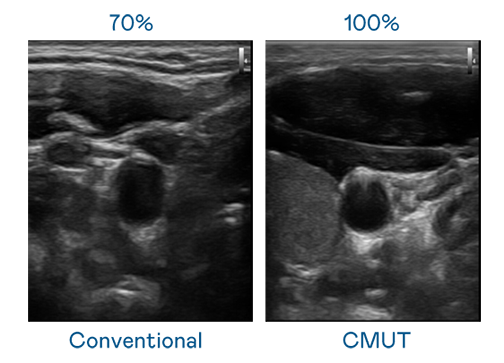

CMUT 技术是一种用电容式微机电元件来产生超音波讯号的技术。与传统 PZT 压电式技术相比,CMUT 频宽增加 30%,更宽频的超音波讯号让影像解析度大幅提升,是实现高影像品质医疗超音波扫描、促进精准医疗发展的关键技术。

大频宽带来超清晰影像

超音波影像的解析度高低,首先取决于探头能发出的讯号频宽。人生就是博 CMUT 可提供高清晰的超音波讯号,提供高频宽、高灵敏度、影像纹理细节更高的超音波影像,协助医护人员缩短影像判读时间及利用精准的医疗影像进行诊断。